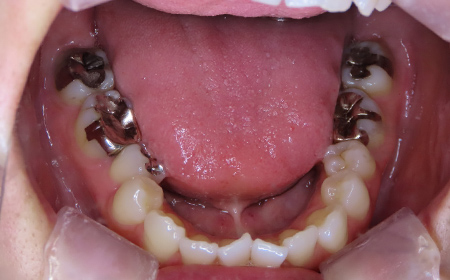

CASE08

Before

After

| 施術名 |

インビザラインコンプリヘンシブを用いた矯正治療(叢生) |

| 治療期間 |

1年 |

| 治療費 |

880,000円(税込) |

| リスク |

マウスピース装置により疼痛・咬合時痛を生じる事があります。割れたり壊れたりする事があります。 |

歯科医師からのコメント

「上顎八重歯が気になる」で来院されました。分析すると、軽度なねじれでしたのでインビザラインGoにて治療をすすめていきました。マウスピースを積極的に使用し、順調に治療がすすんでいきました。仕上がりにとても満足しておられました。